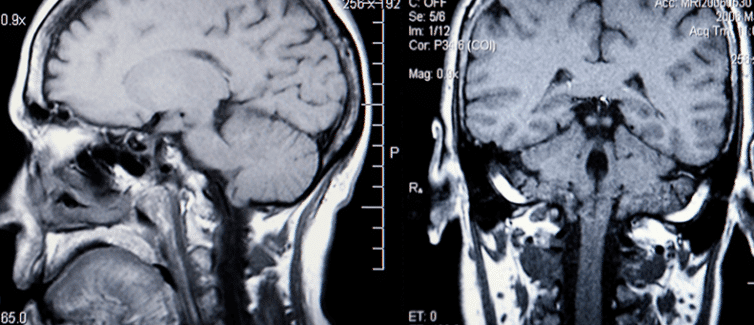

Phình mạch não là tình trạng có một khối phồng ở mạch máu trong não. Phình mạch não có thể vỡ hoặc rò rỉ và khi điều đó xảy ra, nó có thể gây ra đột quỵ xuất huyết.

Chứng phình động mạch não bắt đầu phát triển do thành động mạch mỏng dần. Phình mạch có xu hướng hình thành nơi các động mạch phân nhánh vì những đoạn đó của mạch yếu hơn. Phình mạch có thể hình thành ở bất kỳ vị trí nào trong não tuy nhiên chúng thường được tìm thấy nhiều nhất ở đáy não. Các nhà khoa học không chắc chắn chính xác nguyên nhân gây ra chứng phình động mạch nhưng có một số yếu tố nguy cơ như sau: